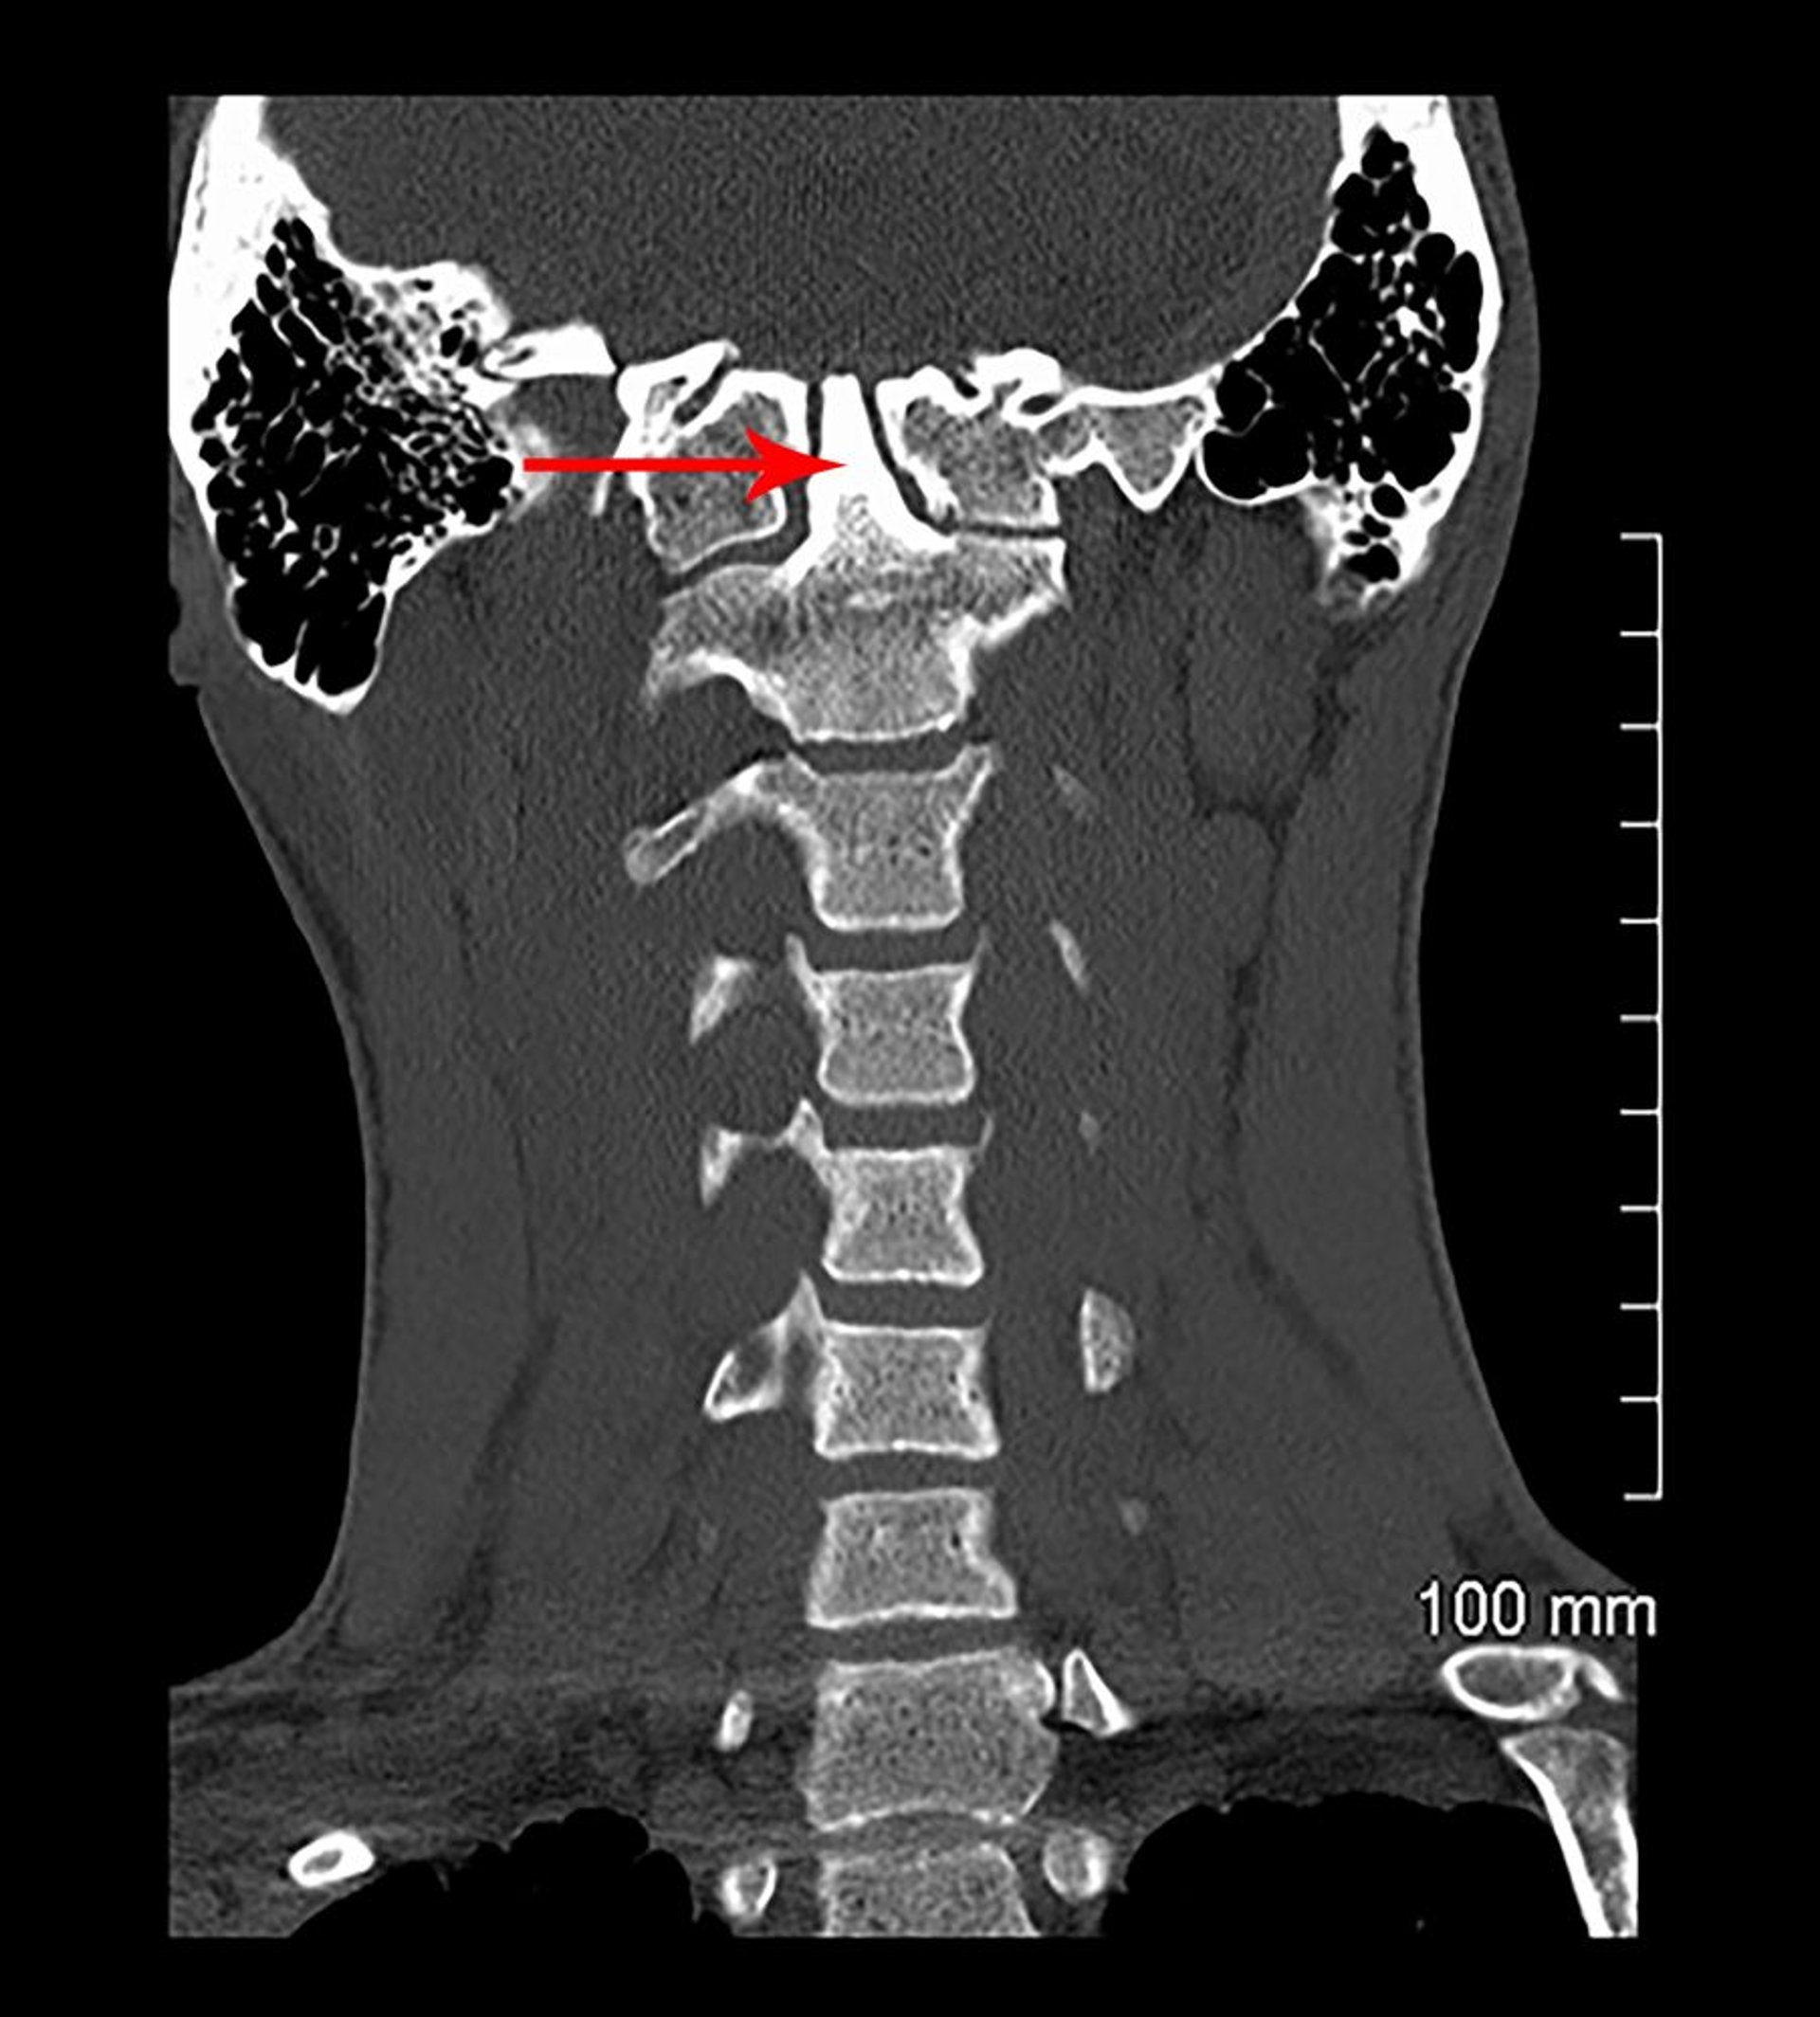

Базилярна інвагінація та вроджена асиміляція (КТ)

In this coronal view of a CT scan, C1 is fused to the skull base (congenitally). The odontoid process (indicated by arrow) extends into the skull base (basilar invagination).